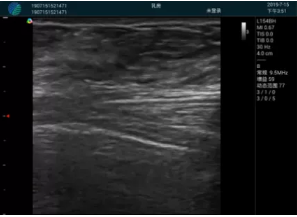

腺體內(nèi)部清晰顯示一低回聲塊影,形態(tài)不規(guī)則,邊界模糊,邊緣呈毛刺狀,內(nèi)部見砂礫樣鈣化

M20引導(dǎo)下穿刺活檢術(shù)